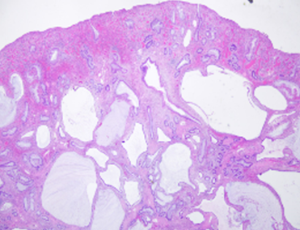

Enteric duplication cysts are rare congenital malformations of the gastrointestinal tract that can be found anywhere along the entire alimentary canal. Duplication cysts share a muscular layer with the adjacent bowel and contain their own mucosal lining which may be that of any part of the alimentary tract.

J Clin Exp Gastroenterol, 2022, Volume Volume 1, Issue Issue 1, p1-4 | DOI: 10.46439/gastro.1.001